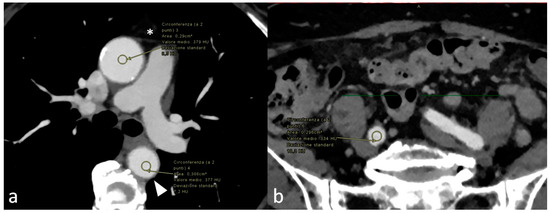

Background: The left circumflex coronary artery from the pulmonary artery is a very rare congenital anomaly with few cases described, so far, worldwide. Case report: An 81-year-old female presented complaining of dyspnea. The transthoracic echocardiogram revealed severe degenerative aortic stenosis in addition to [...] Read more.

Background: The left circumflex coronary artery from the pulmonary artery is a very rare congenital anomaly with few cases described, so far, worldwide. Case report: An 81-year-old female presented complaining of dyspnea. The transthoracic echocardiogram revealed severe degenerative aortic stenosis in addition to a hypertrophied left ventricle with normal function and no wall motion abnormalities. As part of the pre-TAVI planning, she underwent a CT examination, which revealed an anomalous left circumflex artery originating from the right pulmonary artery. The case is currently being managed conservatively. Conclusion: The presented congenital coronary anomaly is, to our knowledge, the first to be described in the literature in this age group (80+). Full article

Show Figures

Figure 1